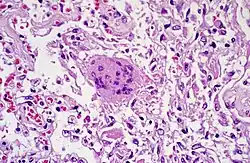

- TOUTON-Riesenzelle - Schaumzellen, bei denen um eine kleine schaumfreie Insel mehrere Kerne ringförmig angeordnet sind, Vorkommen z.B. bei juveniler Xanthogranulomatose, siehe Abb.

- Mehrkernige Riesenzellen - Sie entstehen durch Verschmelzung mehrerer Zellen oder bei inhibierter Zellteilung und kommen sowohl physiologisch als auch im Rahmen pathologischer Prozesse vor.

- Fremdkörper-Riesenzellen - Typisch in Fremdkörpergranulomen, die Zellkerne sind in einem Haufen zusammengelagert

- LANGHANS-Riesenzellen - In Tuberkulosegranulomen, die Kerne sind hufeisenförmig angeordnet

- ANITSCHKOW-Riesenzellen - Bei rheumatischer Myokarditis